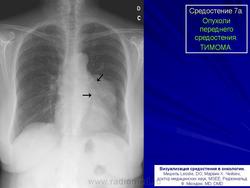

Среди опухолей переднего отдела средостения, вызывающих ограниченное расширение срединной тени, тимомы обнаруживаются чаще всего. Они могут возникнуть в любом возрасте, преимущественно у пациентов на пятом и шестом десятилетии жизни.

Рис. 1а,б. Б-ной К. 1938 года рождения. Обзорные рентгенограммы органов грудной клетки в прямой и левой боковой проекции.

Средостение на уровне передних отрезков IV ребер расширено влево дополнительным образованием, расположенным в среднем и нижнем этажах переднего отдела средостении. Наружные контуры его четкие, поверхность ровная.